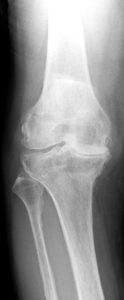

膝関節症重症度5-1